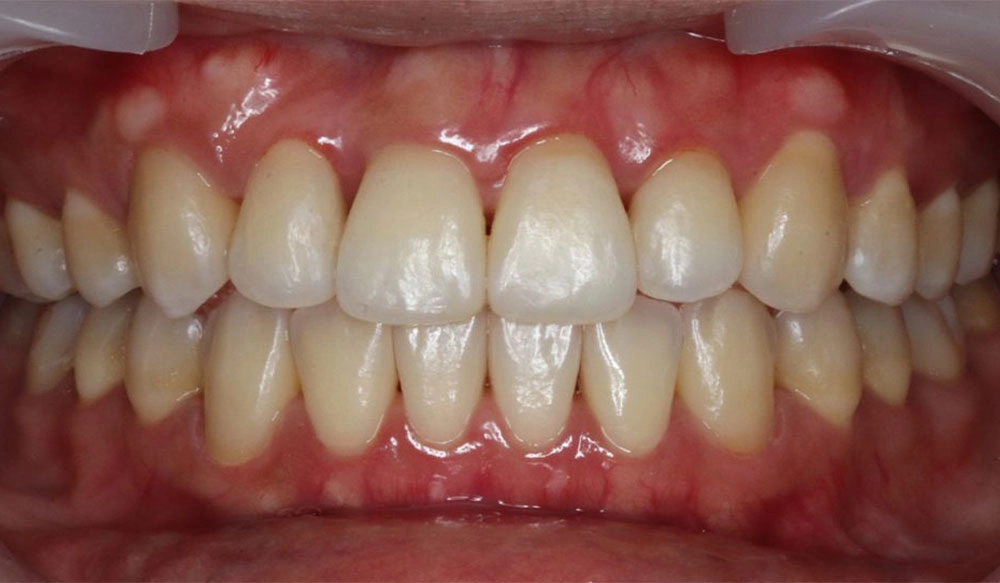

Crowding

Crowding is the condition in which there is a discrepancy between tooth size and space available for the teeth to be aligned in the dental arch

Patient Information:

Age: 17

Gender: female

Invisalign Treatment Option: Invisalign Comprehensive

Total Treatment Time:

29 months